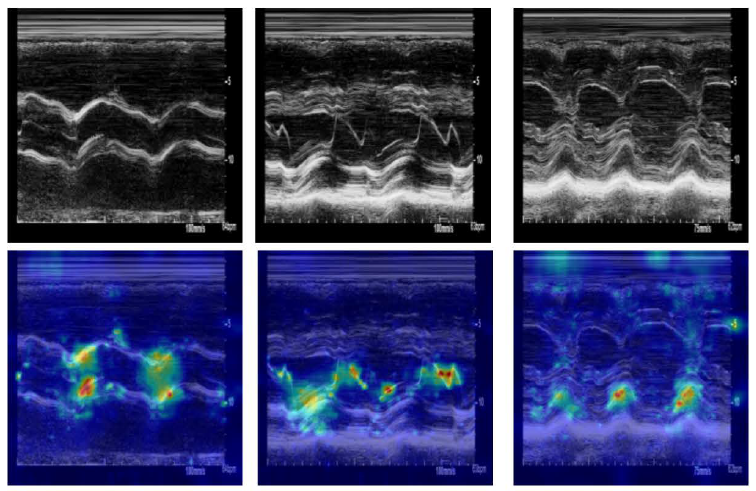

The team asked whether a machine learning model could do what human reviewers often can’t, which is to detect patterns across many simultaneous data streams and integrate them with clinical context. They built a system that analyzes several categories of ultrasound data together: moving video images of the heart’s chambers, valve motion patterns, and Doppler signals measuring blood flow. Those imaging inputs were combined with information pulled from electronic health records, including patient age, body mass index, and standard clinical measurements.

Accuracy also varied across racial groups and across imaging modalities. Spectral Doppler data, one of the ultrasound signal types included in the model, was particularly sensitive to differences between hospitals, suggesting that variation in how that data is collected or calibrated from site to site can affect predictions.